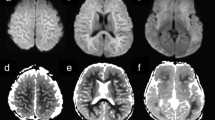

Two neuroradiologists, both having over 10 years of experience in practicing neuroradiology which included interpretation of MRI with DWI, independently reviewed all MR images and were blinded to the results of outcome assessment. One of them is a pediatric neuroradiologist having 1 year of fellowship training in pediatric neuroradiology and over 10 years of experience in practicing pediatric neuroradiology. Different interpretations were solved by consensus. An MRI scoring system using FLAIR imaging was devised to facilitate appraisal of the imaging abnormalities according to a point system (0–12 points) based on the extent of imaging abnormalities (Figs. 1 and 2). The scoring system was as follows: one or two lobes of a cerebral hemispheres = 1 point; three or four lobes of a cerebral hemisphere = 2 points; any one of caudate nucleus, lentiform nucleus, or thalamus on one side = 1 point; any two of these deep gray nuclei on one side = 2 points; one cerebellar hemisphere = 1 point; any part of the brain stem = 2 points. The LRD was defined as a lesion showing hyperintensity on DWI and hypointensity on the ADC map, consistent with cytotoxic edema [18].

A 5-year-old boy with encephalitis 4 days after disease onset. a, b Axial FLAIR images show diffuse hyperintensites in the cerebral cortex, with a higher intensities in the frontal (arrowheads) and parietal (arrows) cortical regions (a) caudate heads (arrowheads), lentiform nuclei (double arrowheads), and thalami (triple arrowheads) (b). Relatively normal signal intensity is noted in the occipital regions. c, d Axial DWI shows hyperintensities indicating restricted diffusion in most of the lesions visible on the FLAIR images